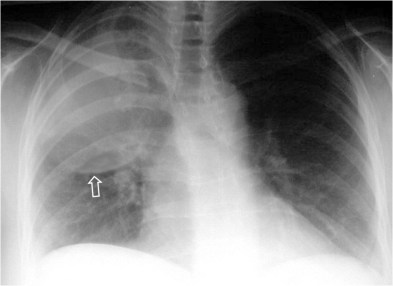

SIGNO DEL BRONQUIO 6

Este signo tiene el mismo significado que el signo del broncograma aéreo. La orientación del bronquio 6 (segmento apical del lóbulo inferior) hace que en vez de ver el broncograma como en otros lóbulos -dibujándose el trayecto bronquial- lo veamos de frente: sólo se ve una imagen redondeada de menor densidad que la consolidación (flecha).

La radiografía lateral confirma la localización en el segmento 6.